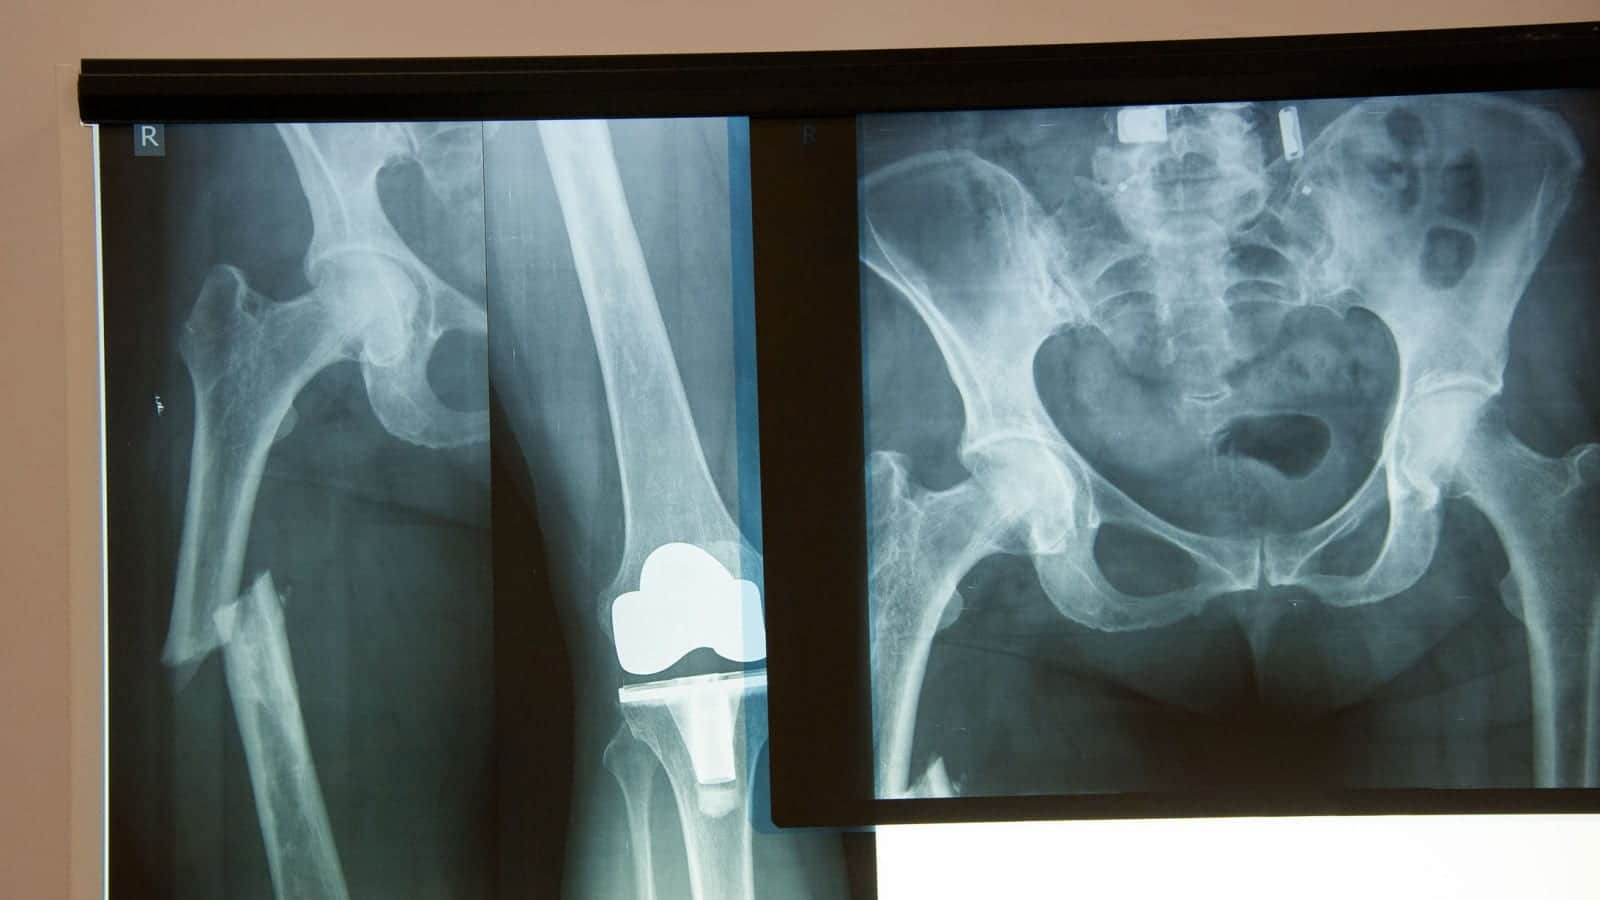

Knee and hip replacements continue to increase in numbers. As baby boomers continue to age and require more medical care, hip and knee replacement options also continue to expand. While it is important to have choices related to medical care, many of the current hip and knee replacement options available on the market are failing. Hip replacement failures have led to the filing of hip replacement lawsuits against the manufacturers of the replacement joints.

Metal on Metal Hip Replacement Failure

Metal on metal hip replacements are generally recommended for younger, more active individuals. However, they are not without their risks. Two of the risks listed by the FDA include infection and joint dislocation. In September 2011, a report was released by the National Joint Registry for England and Wales that stated metal on metal hip replacements had one of the highest failure rates.

The Durom Cup was recalled due to inadequate surgical instructions. Introduced in 2006, the Durom Cup was used in more than 12,000 hip replacements. Hip replacement failure occurred 5.7% of the time. Similar issues have occurred with Zimmer’s NexGen CR-flex knee replacement joint.

In 2008, Stryker recalled two of their hip replacement models: Trident Acetabular PSL Cup and Trident Hemispherical Cup. Side effects of these two hip replacement failures include severe pain, difficulty walking, and broken bones.